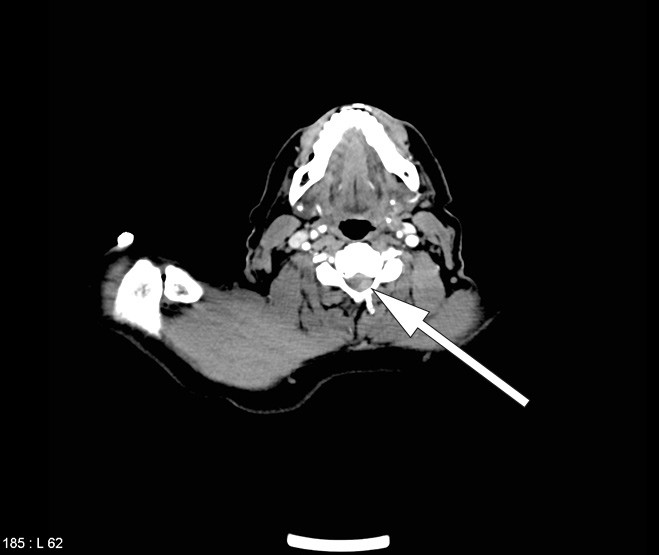

CT-undersøkelsen som ble tatt av totalaorta ved innkomst før trombolytisk behandling, ble initialt tolket som normal, foruten en subtotal stenose i a. subclavia. Ved ny gransking av cervikale avsnitt med noe endring av gråtoneskalaen (window/level) fant man imidlertid at epiduralblødningen var synlig allerede før den trombolytiske behandlingen (fig 3).

Retrospektiv gransking av CT totalaorta viste at epiduralblødningen var til stede allerede før den trombolytiske behandlingen (fig 3). Det er derfor sannsynlig at denne pasientens spinalis anterior-syndrom var forårsaket av epiduralblødningen, og at blødningen ikke var en komplikasjon til behandlingen. Likevel er det mulig at den førte til ekspansjon av hematomet. At pasienten fikk en forbigående bedring etter den trombolytiske behandlingen lar seg vanskelig forklare, men kan skyldes at behandlingen førte til spredning av hematomet i epiduralrommet og dermed en lett dekompresjon av ryggmargen. Bedringen var kortvarig, og pasienten ble raskt dårligere etter trombolytisk behandling. Da det epidurale hematomet ble oppdaget, ble operasjon raskt igangsatt. Ved hematomer som trykker på ryggmargen og fører til nevrologiske utfall, avhenger prognosen av rask kirurgisk dekompresjon (16, 19).